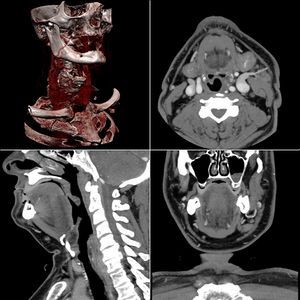

التصوير المَقْطَعي الحاسوبيX-ray computed tomography نظام تصوير بالأشعة السينية، يُسْتخدم لتصوير مختلف أجزاء الجسم مثل الرأس والقلب والبطن. ويستعين الأطباء بالتصوير المقطعي الحاسوبي على تشخيص الأمراض وعلاجها. وتسمى هذه التقنية أيضًا التصوير المقطعي المحوسب أو التصوير المقطعي المحوري المحوسب.

ويستعمل الأطباء فحوص التصوير المقطعي الحاسوبي لتشخيص كثير من الحالات مثل الأورام والإصابات وتجلطات الدم وكسور العظام. ويساعد التصوير المقطعي الحاسوبي أيضًا في معالجة بعض الأمراض، التي قد تتطلب جراحة بطريقة أخرى. فمثلا،ً يمكن للأطباء استعمال التصوير المقطعي الحاسوبي لإرشادهم إلى إدخال القثطار (أنبوب رفيع) إلى خُرّآج في الجسم لسحب الصديد من المنطقة الملوثّة.

يمكن للأطباء أن ينظروا داخل جسم المريض عن طريق طلب إجراء مسح للعظام والأوعية الدموية والأدمغة والأنسجة الرخوة بفضل ماسح التصوير المقطعي الحاسوبي (CT). بعد إجراء أول فحص طبي بالأشعة المقطعية للمريض في عام 1971، استخدم أطباء الأشعة عمليات المسح لتشخيص الأورام والصدمات والتخطيط للعلاج الطبي والجراحي والإشعاعي في جميع أجزاء جسم الإنسان تقريباً.

وتستخدم في تصوير الشريان والأوردة بدل من الأشعة التداخلية وهي أكثر أمانًا وتستغرق وقت قصير وتشخيص الجلطة الرئوية بدل التصوير النووي